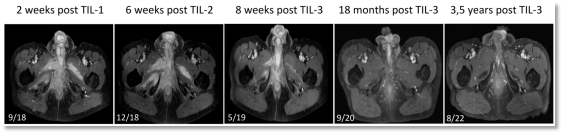

在两次治疗均出现生化指标反弹和影像学检查不理想的结果后,医生和患者并没有放弃。2019年1月,他们再次进行了穿刺取样,制备了TIL细胞,这次回输了比前两次更大的细胞量(8×109个细胞),并联合使用了抗PD-1治疗药物帕博丽珠单抗。如下图所示,这次的坚持给这位年逾七旬的肿瘤患者带来了“新生”,PSA和NY-ESO-1抗体自输注后持续下降,影像学检查显示输注后第8周肿瘤显著缩小,第18个月完全消退,截止论文撰写,患者肿瘤的完全消退状态已经持续了超过3.5年!

影像学检查显示:首次TIL输注后两周和第二次TIL输注后六周肿瘤未有明显缩小;第三次TIL输注后8周肿瘤明显缩小,第18个月肿瘤完全消退,3.5年仍处于完全消退状态。